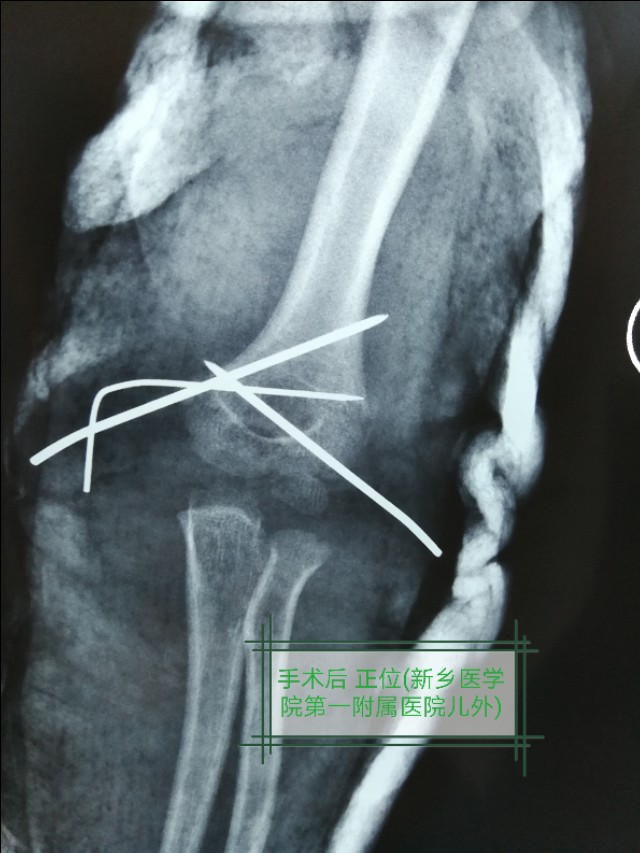

例二:闭合复位,经皮穿针固定